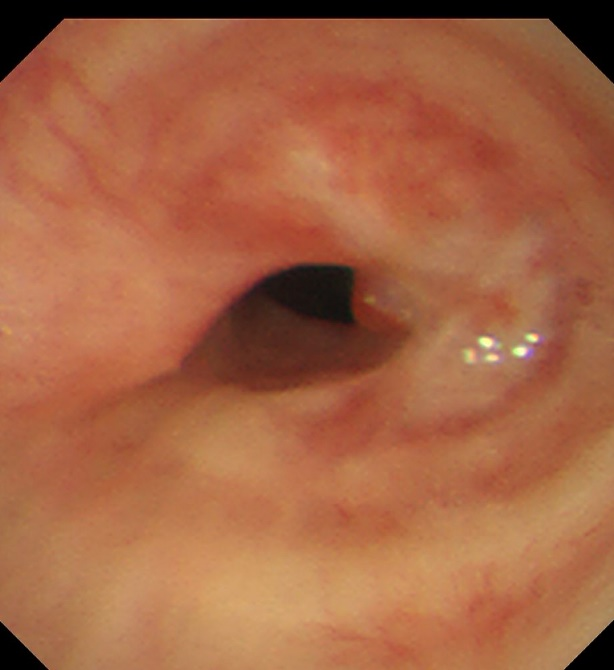

患者,女,50岁,因“外伤后呼吸困难2月”来到亚洲色吧 全科医学科治疗。患者2月前因外伤致气管撕裂,在当地医院行气管修补术,术后出现进行性加重呼吸困难。患者来到我院住院后,稍微活动就会感到气促,已不能活动,肺功能显示重度阻塞性肺通气功能障碍,胸部CT显示气管下段重度狭窄,支气管镜检查显示气管下段距隆突2cm处重度瘢痕狭窄,最窄处仅4mm,随时都会发生窒息甚至猝死,手术迫在眉睫!

气管下段狭窄治疗前